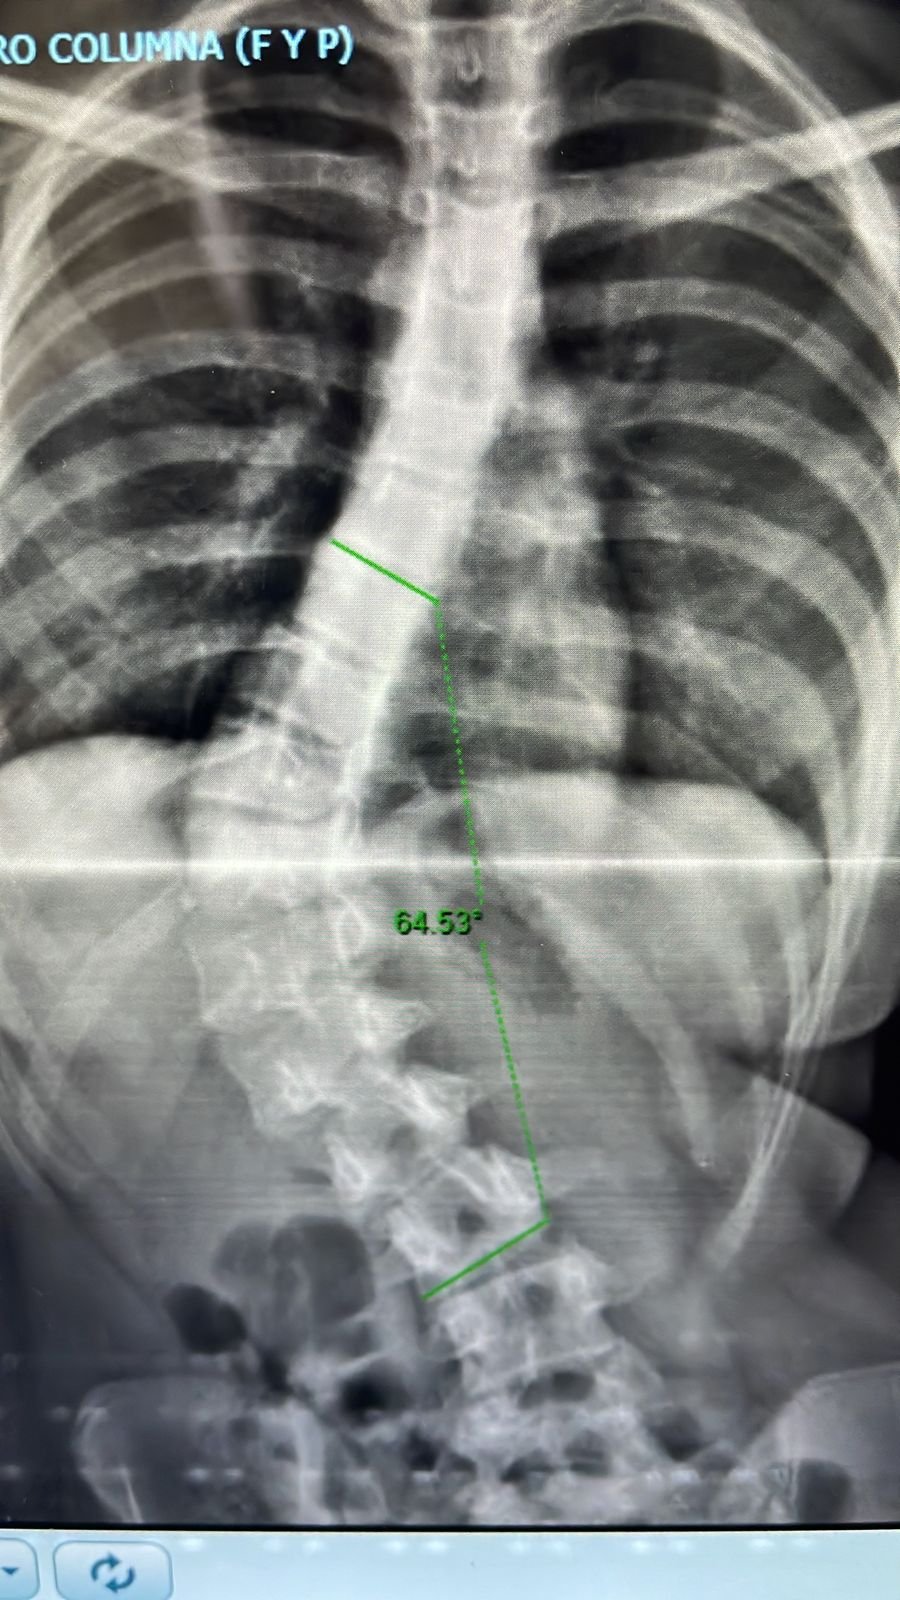

Escoliosis Progresiva.

“ Soy María Mercedes a los 11 años me diagnosticaron escoliosis, empecé con 40 grados, y ya a los 13 llegué a tener casi 70 grados. Me avergonzaba usar remeras ajustadas, practico patín artístico dese los 3 años, y a los 12 había saltos y figuras que no me salían debido a la severidad de la escoliosis .A los 13 años, el 20 de enero del 2022, fui operada por el Dr. Pablo Fiorillo. La operación fue todo un éxito, el Dr. me brindó contención y seguridad en todo momento, súper recomendable. En mayo del 2022, ya retomaba mi deporte patín artístico. Durante todo el año 2023 seguí realizando patín artístico y competencia individual, pudiendo participar en campeonatos regionales y provinciales. Gracias a la excelencia profesional del Dr., hoy con 15 años puedo llevar una vida normal y seguir patinando”